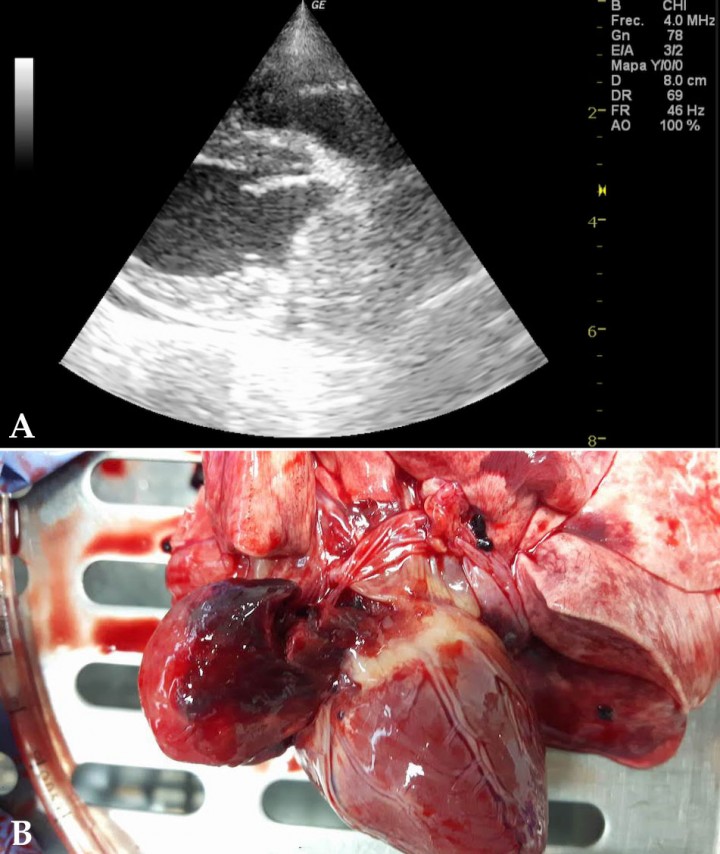

Tanto el tamaño como la localización puede ayudar al diagnóstico, siendo siempre necesario la citología o la toma de biopsias para la confirmación del diagnóstico.27 Las masas cardiacas pueden tener cualquier localización cardiaca (Fig. 7).

Figura 7

(A) Ecocardiografía en corte paraesternal derecho, eje largo, cuatro cámaras. Imagen compatible con masa en atrio derecho (entre flechas). (B) Imagen macroscópica donde se aprecia la visualización de masa en aurícula izquierda post mortem.